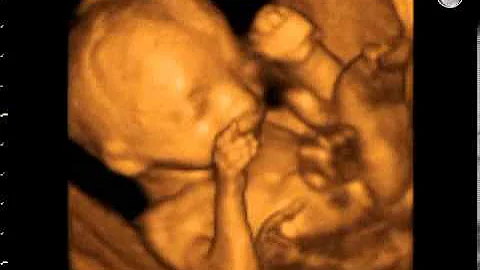

Your Pregnancy: 22 Weeks

"You're probably feeling pretty good these days. Your waistline may have vanished but most likely you can still bend over easily, ...